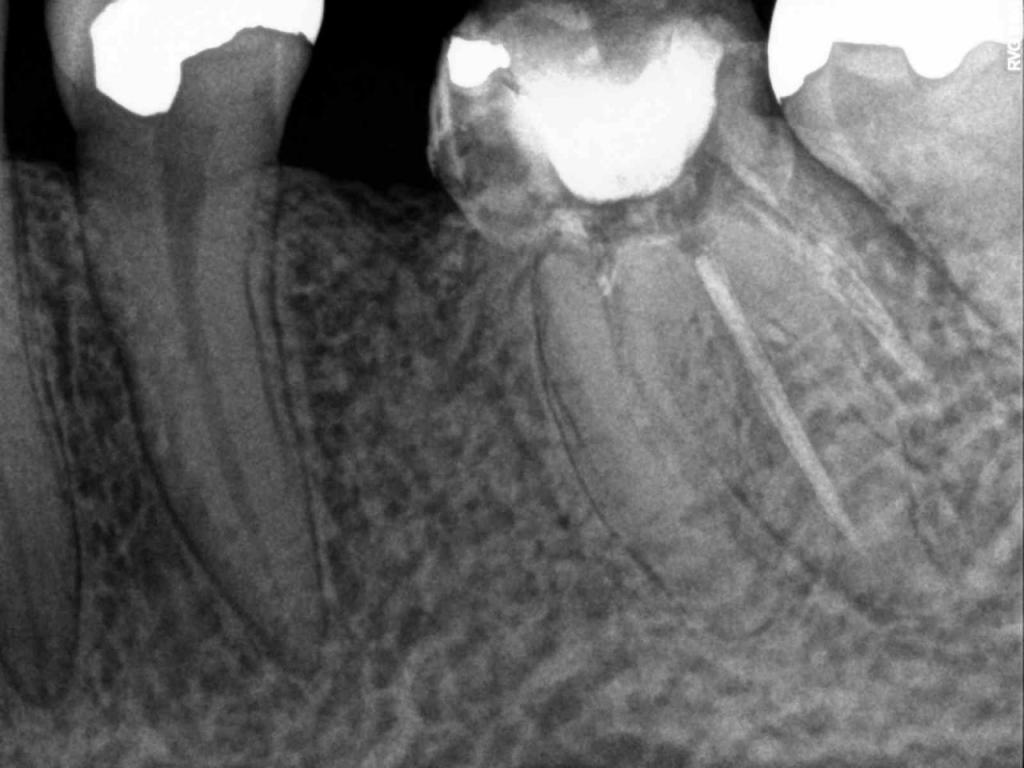

Although the primary use of visual documentation is for patient charts, dental images provide a meaningful way to communicate with patients about their care needs. Digital imagery is a vital tool for educating patients and an essential way to share information with office staff, colleagues and referring doctors. Digital technology has allowed Southcenter Endodontics to enhance our practice and improve the delivery of care to our patients. Below you will see images of “Before” and “After” scenarios. By clicking on a thumbnail image below, you will be able to see and a larger view of the x-ray taken at Southcenter Endodontics and notations made regarding each film.